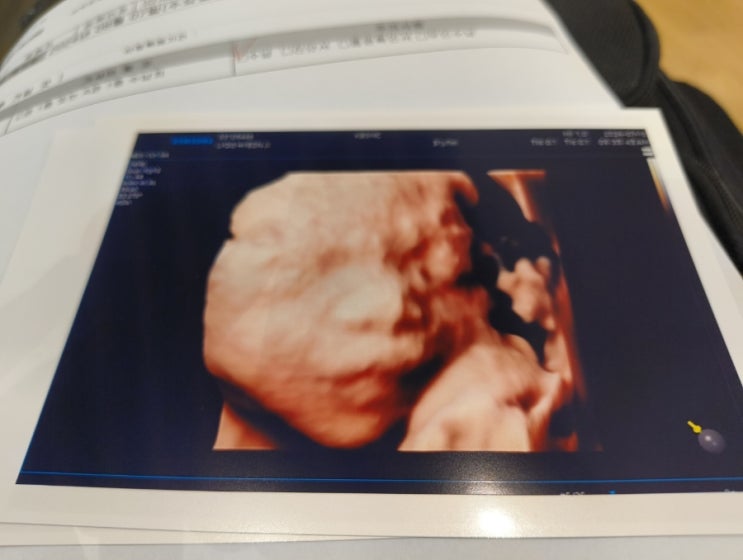

[임신기록] 20~23주차 일기 _ 정밀 초음파 검사, 체중 조절, 바나나로 자라난 아기 ?

❣️체중 조절하기 체중이 너무 빨리 늘고 있어서 충격받았던 날. 지난 번 방문 때보다 3kg가 늘어있었다. ...